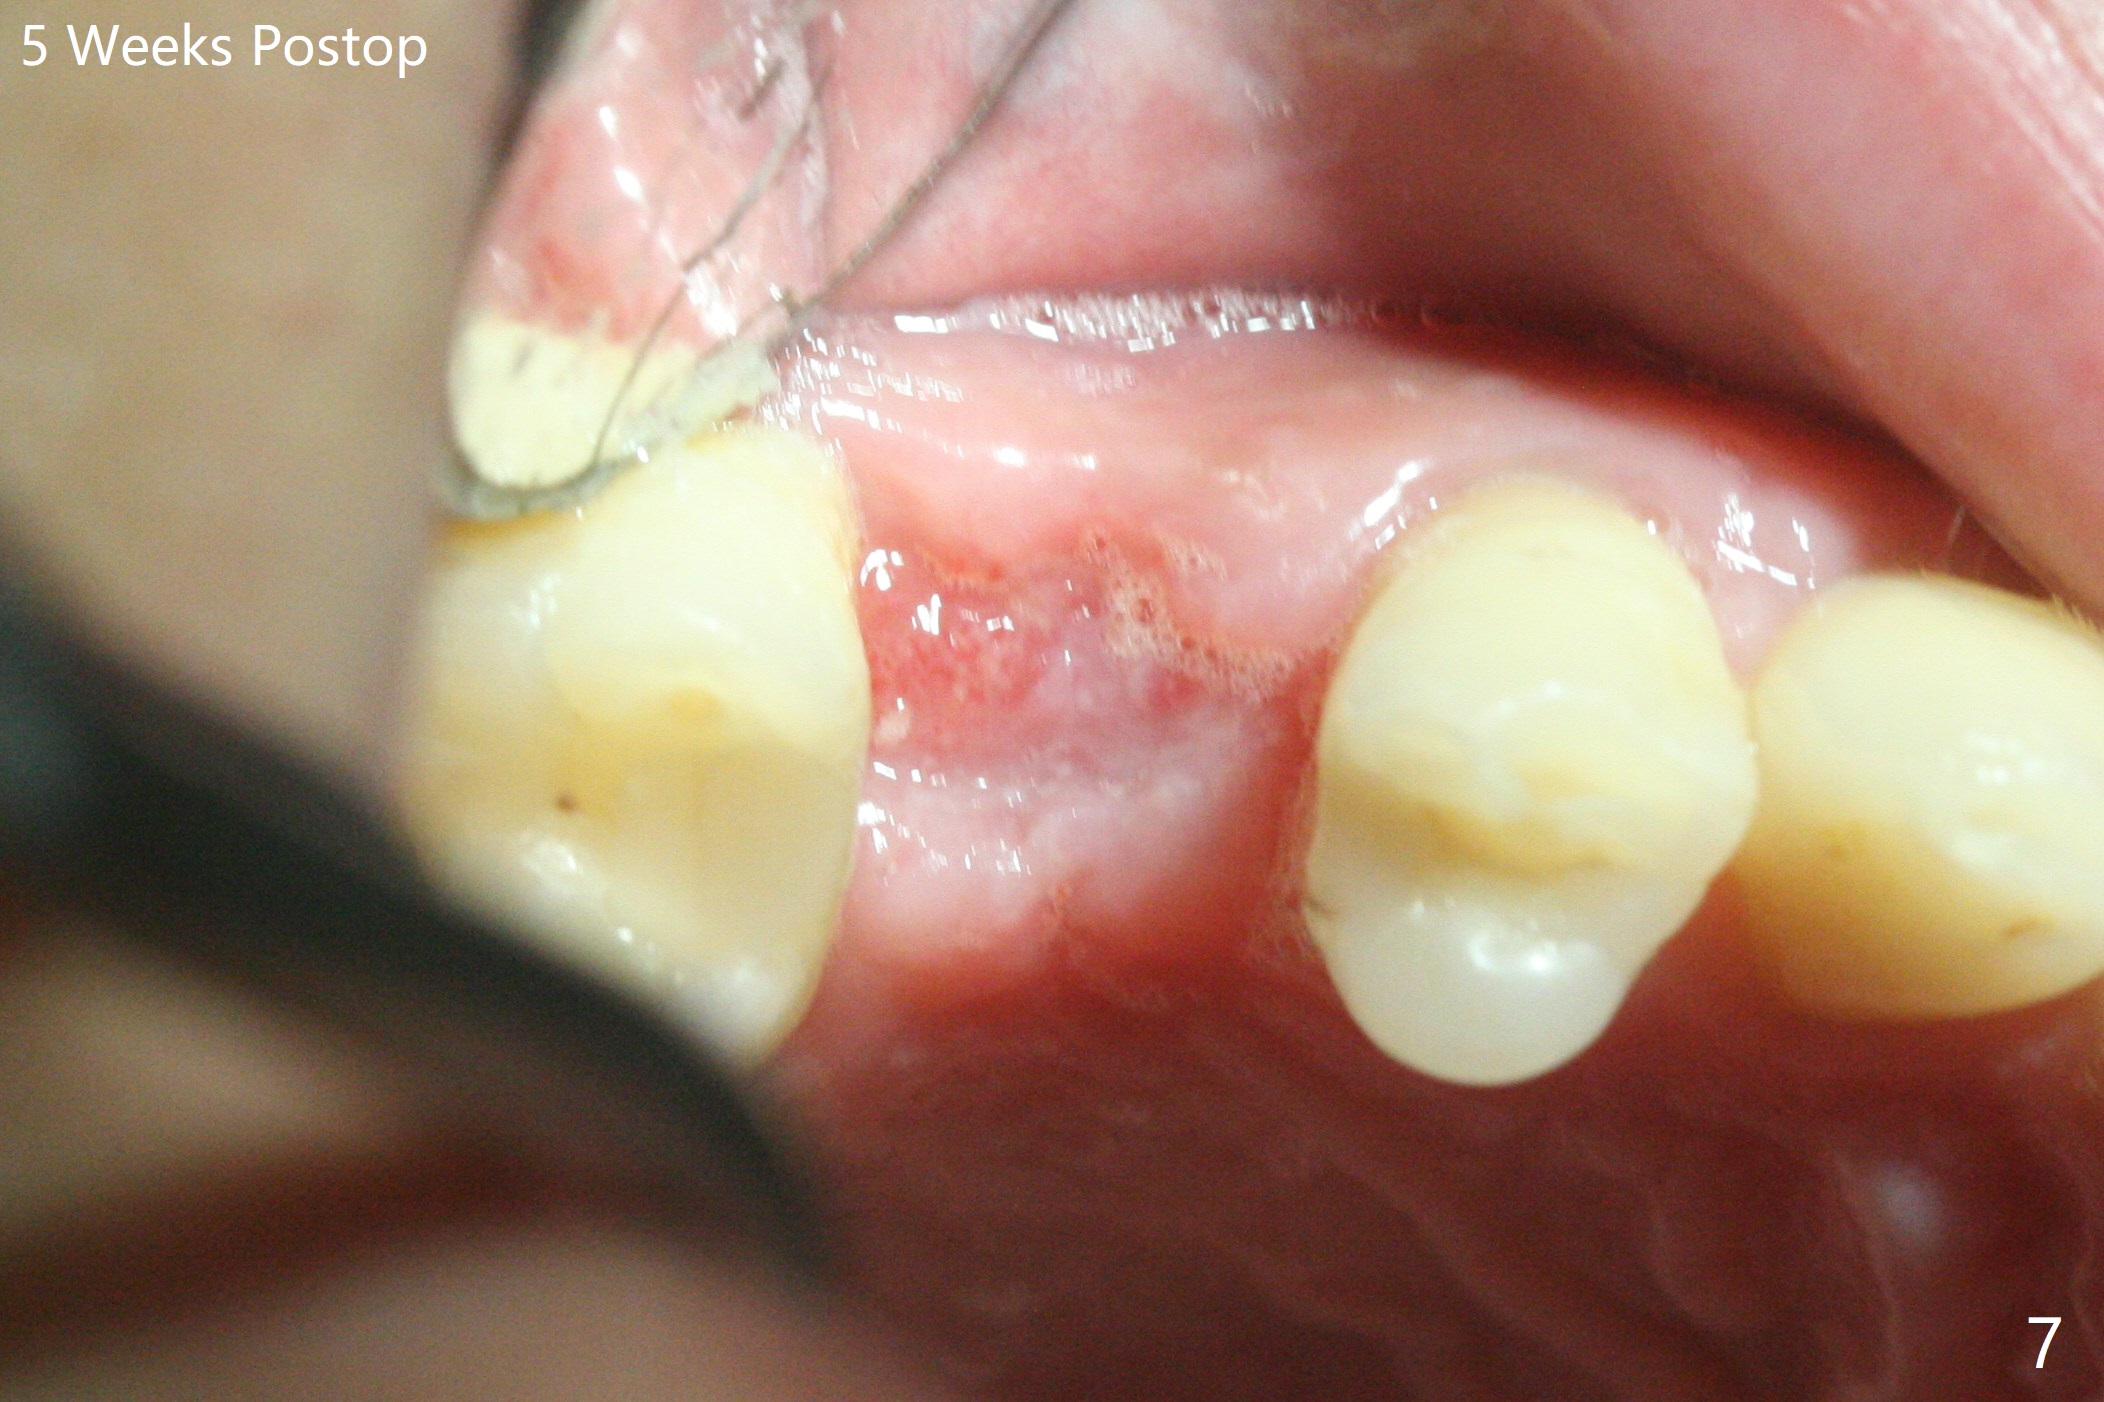

尽管没有任何症状,右上5牙冠粘固后2年5个月,牙冠与基台取出(没有使用扳手,说明基台未完全就位),切开,去除少量肉芽组织,仍然发现植体螺纹暴露(图一),使用一种叫I Brush 钛合金刷子清洁后,放置粘性骨块(图二: S),它坐在牙槽嵴上仿佛非常安稳,多么象马鞍(Saddle)。覆盖一张PRF膜和一小张Cytoplast(不可吸收膜,Osteogenics (company) 图三:箭头),使用PTFE缝线(与Cytoplast同样一种材料)缝合。术后即刻根尖片显示骨粉服服帖帖地坐落在植体和牙槽嵴上(图四:*)。最后覆盖牙周敷料。后者术后十天左右脱落,伤口愈合正常,颊侧瘘道仿佛消失,颊侧骨壁好像不再凹陷了(图五,六)。术后5周,膜已经脱落,缝线撤除后,伤口好像二期愈合,但愿肉芽组织下面骨粉尚未损失太多。术后三个月根尖片显示骨粉减少(图八)。不可吸收膜脱落可能造成骨粉流失。应该做减张缝合。术后4.5个月颊侧骨壁又凹陷(图九:箭头,需要decortication),但是uncover时植体周围都有骨质包绕,术后咬翼片也证明近中,远中骨质接触植体(图十:由于找不到合适愈合基台,直接放置基台和牙冠)。粘固后2.5个月虽然颊侧骨板凹陷,但是没有植体周围炎迹象(图十一)。